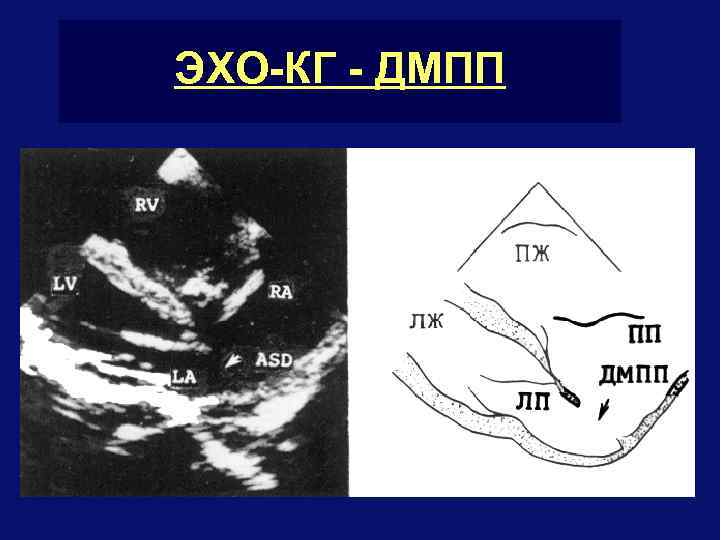

ЭХО-КГ - ДМПП